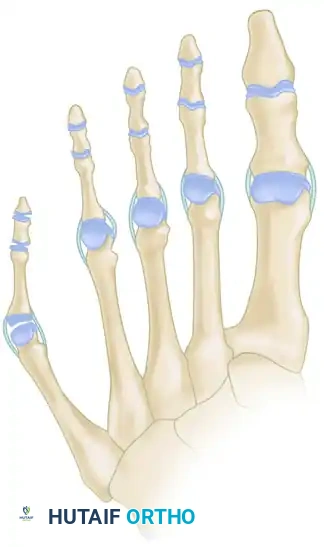

Classification of Bunionette Deformity

The classification system proposed by Cohen and Nicholson is the most widely accepted framework for categorizing bunionette deformities. It is based entirely on the structural radiographic appearance of the fifth metatarsal and directly guides surgical intervention.

Type I: Enlarged Metatarsal Head

Type I is characterized by an isolated enlargement or lateral prominence of the fifth metatarsal head. The 4-5 IMA and the lateral deviation angle remain within normal limits. This is often described as a "dumbbell-shaped" metatarsal head.

FIGURE 83-41A Type I, lateral prominence of the metatarsal head.

Type II: Lateral Bowing of the Metatarsal Shaft

Type II features an abnormal lateral bend or bowing of the distal third of the fifth metatarsal shaft. The 4-5 IMA is normal, but the Lateral Deviation Angle (LDA) is significantly increased.

FIGURE 83-41B Type II, lateral bowing of the fifth metatarsal.

Type III: Widened 4-5 Intermetatarsal Angle

Type III is the most common variant. It is characterized by a divergent fifth metatarsal shaft resulting in an increased 4-5 IMA (greater than 8 degrees). This divergence significantly widens the forefoot (splayfoot).

FIGURE 83-41C Type III, widening of the 4-5 intermetatarsal angle.